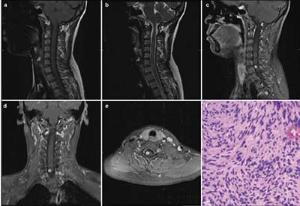

20171023160911  Figure 1 (a) Sagittal T1-weighted magnetic resonance image demonstrating an isointense lesion. (b) Sagittal T2-weighted magnetic resonance image demonstrating a slightly hyperintense lesion, with swelling surrounding it. (c–e) Sagittal, coronal, and axial T1-weighted magnetic resonance images, with gadolinium contrast, demonstrating homogeneous enhancement of the tumor. The tumor appears as a solid mass, located to the right side of spinal cord, with clear margins. (f) Hematoxylin and eosin staining from the biopsy of the mass showing bipolar spindle cells with nuclei arranged in a palisade pattern (Hematoxylin & Eosin stain; magnification, ×100).